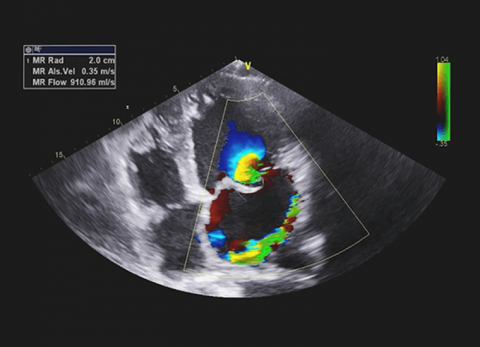

Zastawka mitralna

Wideo Echokardiografia od podstaw. Przypadek 5: Zastawka mitralna cz. 2

prof. dr hab. n. med. Piotr LipiecDokładne omówienie przypadku z obrazami z echokardiografii. Zastosowanie w codziennej praktyce i podstawy analizy obrazów echokardiografii i ich inter...